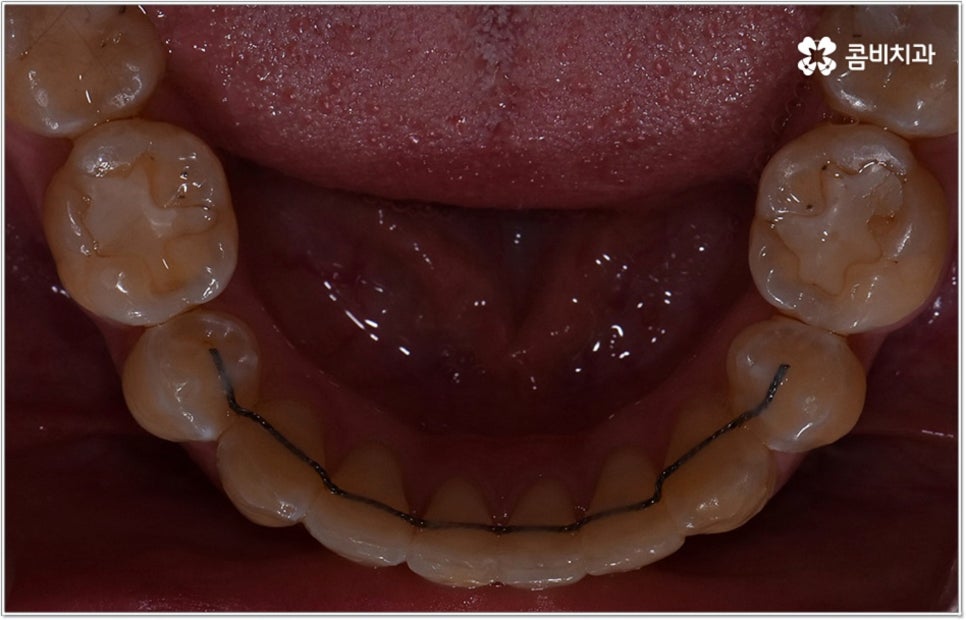

잘 아시다시피 교정이란 치아에 교정 장치 (브라켓) 를 부착하고 와이어에 교정력을 걸어 필요한 방향으로 치아를 이동시킴으로써 고른 치열과 올바른 교합을 가진 정상적인 구강 구조를 회복하는 치과 진료를 의미하는데요, 말씀드린 것처럼 부정교합에는 다양한 형태가 있고 또한 환자분들마다 심각한 정도가 모두 다르기 때문에 현 상태를 면밀하게 체크하고 맞춤 교정 치료 계획을 세우는 것이 무엇보다 중요하다고 할 수 있습니다. 즉 3D CT 와 같은 정밀 진단 장비를 갖추고 있는 치과에서 교정 관련 임상 경험이 풍부한 숙련된 의료진과 함께 치료를 진행하는 것이 필수적이라고 할 수 있어요. 전체 방향 및 세부 플랜을 세울 때 각 환자에 맞게 치아의 이동 속도에 무리가 가지 않도록 하기 위해서 연령이나 발달 상황, 진행 상황을 면밀하게 살펴보는 것이 필요하며 또한 구강 내 공간 유무 및 부정교합 정도에 따라 발치 또는 비발치치아교정 여부를 결정하게 될 거예요.

만약 치아가 이동할 범위를 계산해 봤을 때 공간이 충분하다면 굳이 치아를 뽑지 않고 비발치치아교정 과정으로 치료할 수 있어요. 제일 뒤에 있는 어금니를 더 후방으로 이동시키거나 치간 삭제, 악궁확장장치 등으로 치아 사이를 벌려서 이동 공간을 확보할 수 있으면 비발치치아교정 이 가능한 거예요. 이 때 부정교합이 심각하거나 악골이 치아에 비해 많이 작은 경우, 구조적인 원인을 개선할 필요성이 있는 경우 등 발치 교정을 하는 것이 꼭 필요한 케이스라면 치아를 뽑아주어야 하며, 환자분들의 상황에 따라 다르지만 보통은 소구치를 발치하는 경우가 많이 있습니다.

발치 여부 외에도 사용할 장치 종류, 교정 기간 등 여러 세부적인 사항들 역시 정밀 검진 결과 및 사전 상담 내용 (예를 들어 환자분들이 상시 복용하시는 약이 있는지, 식습관이나 버릇 (ex. 이갈이) 같은 것은 어떠신지 등등 생활 전반에 대한 부분) 을 꼼꼼히 확인한 후 이를 전체적으로 고려하여 맞춤 플랜을 세우고 교정 치료를 시작하는 게 중요하며, 진행 역시 무리하지 않게 환자분들의 상황에 맞출 필요가 있으므로 의료진이 중간에 교체되는 일 없이 처음부터 끝까지 책임 진료할 수 있는 곳에서 치료를 하시길 권유드리고 있어요. 또한 체계적인 시스템을 갖추고 있는 곳이어야 결과의 지속성을 보다 높일 수 있는 사후 관리까지 철저하게 받을 수 있으니 이런 부분도 잘 체크해 보시면 좋을 거예요.